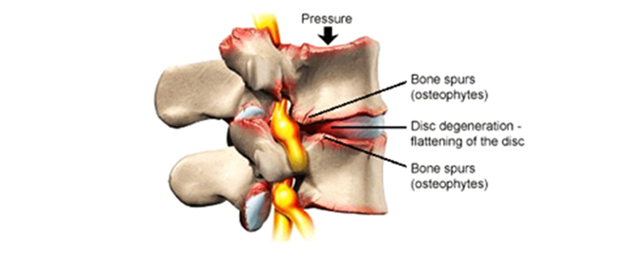

Si pasojë e kësaj, vjen deri te ngushtimi i hapësirës mes dy unazave (stenoza) si dhe paraqitja e osteofiteve, që qon në degjenerim të unazave.

Së pari, nga bërthama fillon të humbet uji e pastaj disku fillon dhe bëhet më i fortë. Kështu, e humbë aftësinë e absorbimit të ngarkesës (forcës), pastaj mbështjellësi fibrozë rreth diskut e humb aftësinë e elasticitetit, anulusi dobësohet dhe, si pasojë e kësaj, vjen deri te kërcitja e tij dhe rrjedhja e përmbajtjes xhelatinoze nga bërthama e diskut jashtë. Kështu, së pari fillon si diskus herni, e me pastaj vjen duke përfunduar në pasojat e diskut të degjeneruar.

Pasi një disk të humbë përafërsisht 80% të lëngut (ujit) të tij, atëherë ai quhet i degjeneruar. E tërë kjo mund të shkaktojë radikulpati, stenozë apo ngushtim të kanalit spinal dhe artrozë të hapësirës mes unazave, e cila mund të jetë e përcjellur edhe me humbje të masës kockore minerale dhe dhënie të deformimeve të shtyllës kurrizore si pasojë e këtyre ndryshimeve. E gjithë kjo, mund të shpie edhe në dhembje të shtyllës kurrizore.